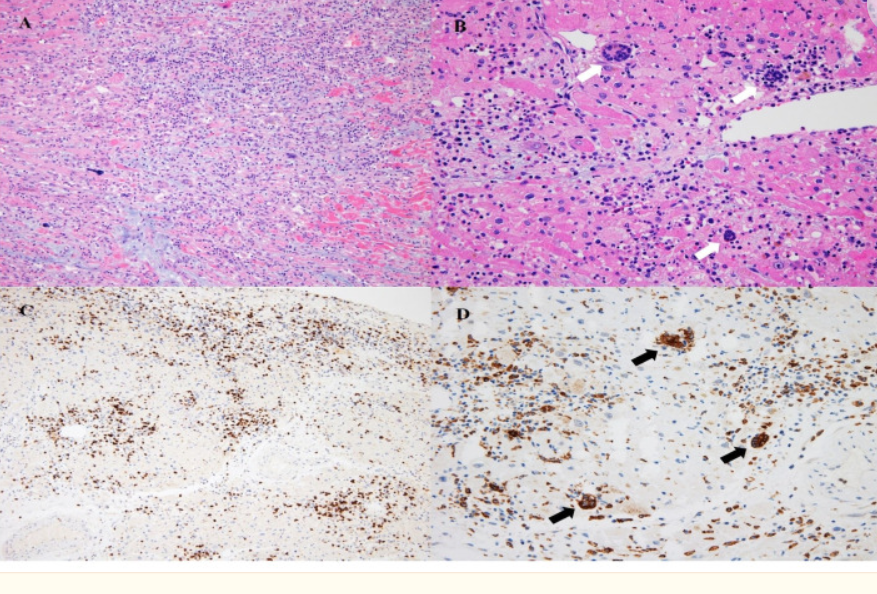

Ici des syncytia visibles dans les pneumocytes de personnes décédées du COVID

elifesciences.org/articles/65962…

L’histopathologie montre la nécrose (mort des cardiomyocytes), une forte infiltration de macrophages, lymphocytes T, quelques éosinophiles et surprise des cellules géantes d’origine monocytaire (CD68+) … mais d’où viennent-elles et que deviennent-elles?

Cette étude montrait déjà en avril 2021 que les cellules immunitaires de différents types exprimant la spike pouvaient fusionner entre elles pour former un syncytium et finir par mourir …